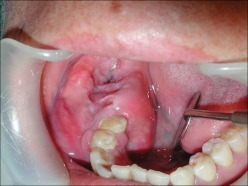

Benign odontogenic tumor of epithelial origin that exhibits a locally aggressive behavior with a high level of recurrence, being believed theoretically to come from dental lamina remains, the enamel organ in development, epithelial cover of odontogenic cysts or from the cells of the basal layer of the oral mucosa.

We present a case of a 24-year-old man with an ameloblastoma of the mandible, in whom a soft tissue lesion was noted at pre-operative axial computed tomography (CT).